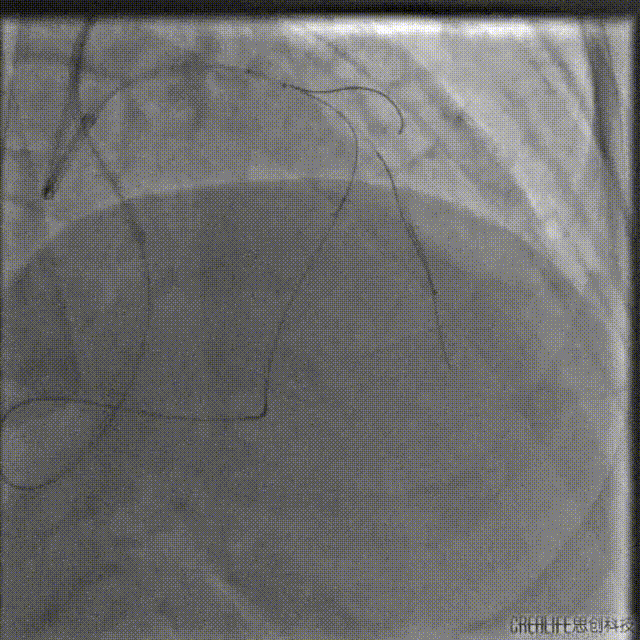

启动逆向开通

考虑间隔支侧枝纤细且存在显著成角迂曲,选择1.5F HighTrack微导管作为逆向微导管,支撑SION导丝进入侧枝。

SION导丝受限于严重迂曲无法通过,遂更换为SUOH 03导丝,通过侧枝走行至LAD闭塞处后反向前送至LAD远段,HighTrack微导管通过侧枝跟进至分叉处。

逆向导丝更换为P200后仍不能突破CTO远端纤维帽至LAD近段,遂调整前向导丝Kissing逆向导丝进入间隔支,送入1.5mm球囊扩张LAD至间隔支。

试图用SUOH03 逆向Knuckle至LAD近段未成功,遂将SUOH03导丝推送至LAD远段。